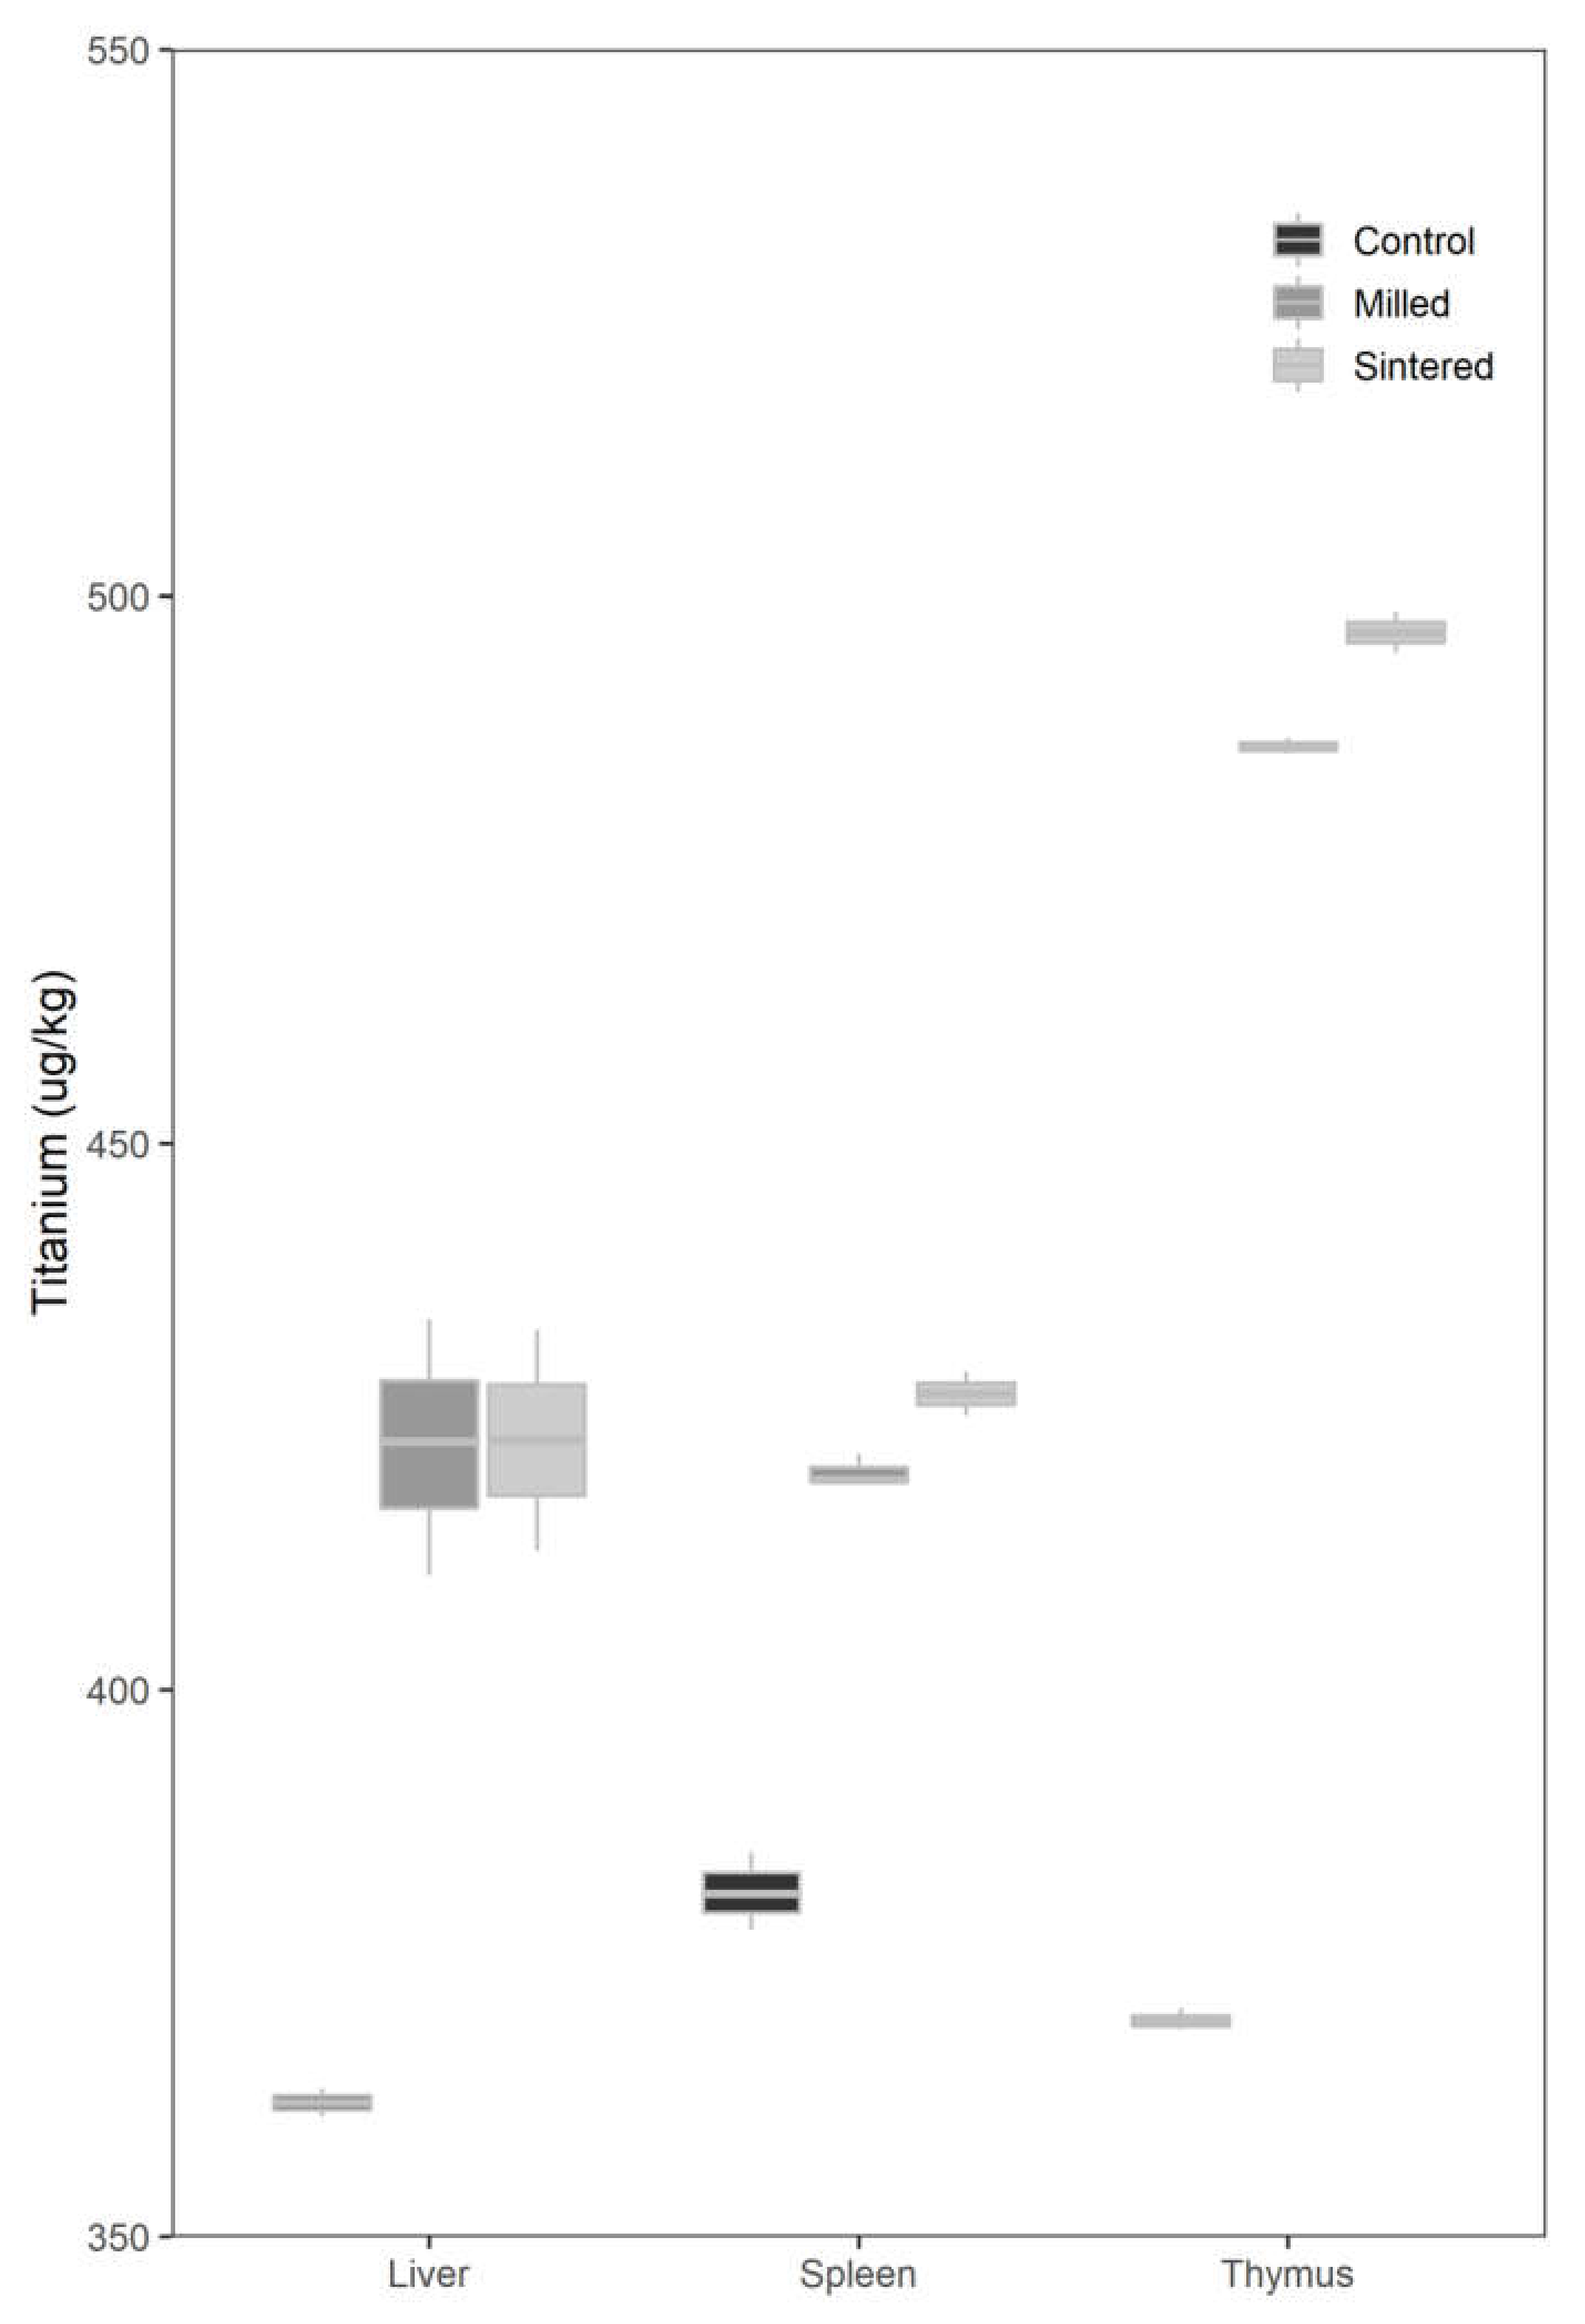

2.2. Analysis of Titanium Concentration in Organs

2.2.1. Liver

2.2.2. Spleen

2.2.3. Thymus